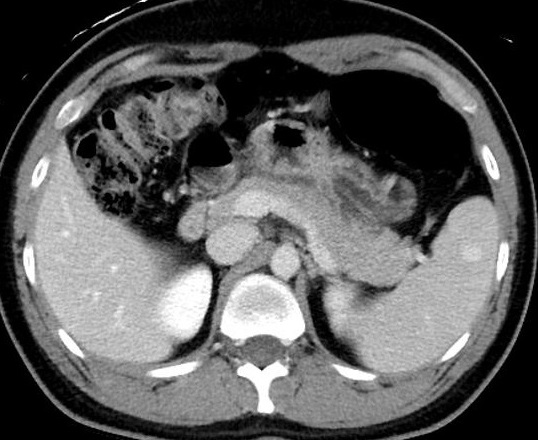

Image radiologique TDM en

coupe axial d'une rate surnumeraire multiple au bord

anterieure de la rate . Aspect lesionaire est

deux nodules isodensite nette et lisse situe a

bord anterieure de la rate principale ( A ) . Sur

les exposes avec contrast intraveineuse ( B ) elles

se rehaussent heterogene a precoce et puis homogene

au temps d'evacuation |